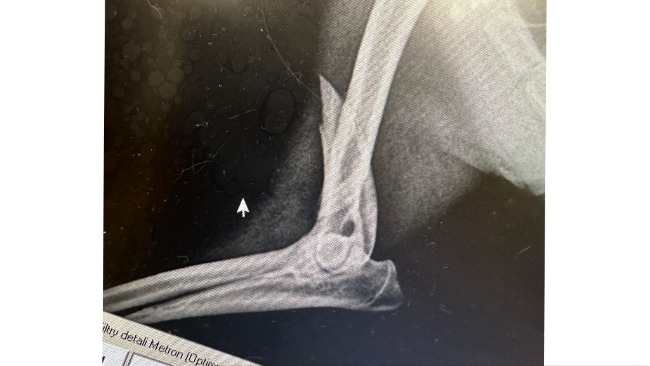

Od razu trafił do lecznicy gdzie wykonano zdjęcia RTG i dokładnie go przebadano. Psiak doznał złamania przedniej, prawej łapy z przemieszczeniem, ma duża otwartą ranę na tylnej łapie oraz otarcia na pyszku. Na szczęście nie ma obrażeń wewnętrznych ani krwotoku.

Przednia łapa musi być jak najszybciej złożona przez chirurga-ortopedę na specjalną blachę i ustabilizowana śrubami. Każdy dzień zwłoki spowoduje że złamanie będzie się przemieszczać, a psiak będzie odczuwać co raz większy ból.